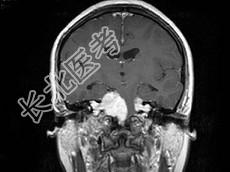

- 单项选择题女,22岁, 胸背部及头皮下多发红色丘疹状突起,伴头痛, 听力下降半年,行头颅MRI平扫及增强扫描如图, 最可能的诊断为 ( )

D、神经纤维瘤病NF-Ⅱ型